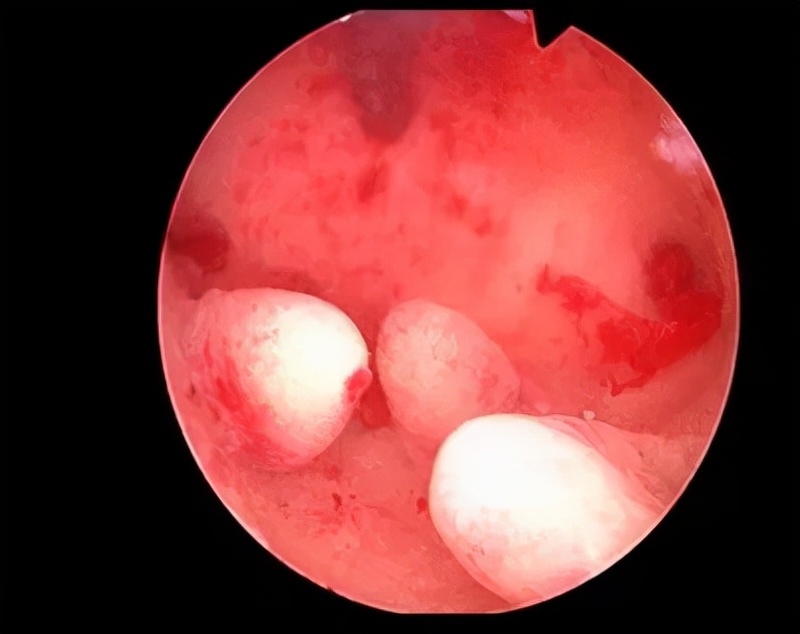

2.黏膜下子宫肌瘤

3.子宫内膜息肉

但是,这些疾病不都是单独存在的,有些患者可能同时几种疾病共存,共同引起异常子宫出血。